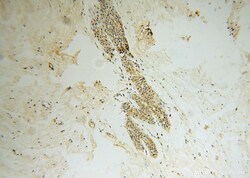

Immunohistochemistry

16294-1-AP IHC